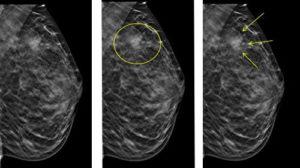

Bildgebende Verfahren

Die Diagnose von Mikroverkalkungen erfolgt in der Regel durch bildgebende Verfahren wie die Mammographie oder die Kernspinntomographie. Bei Verdacht auf eine bösartige Ursache werden weitere Untersuchungen wie eine Biopsie durchgeführt, um Gewebeproben zu entnehmen und diese auf Krebszellen zu untersuchen.